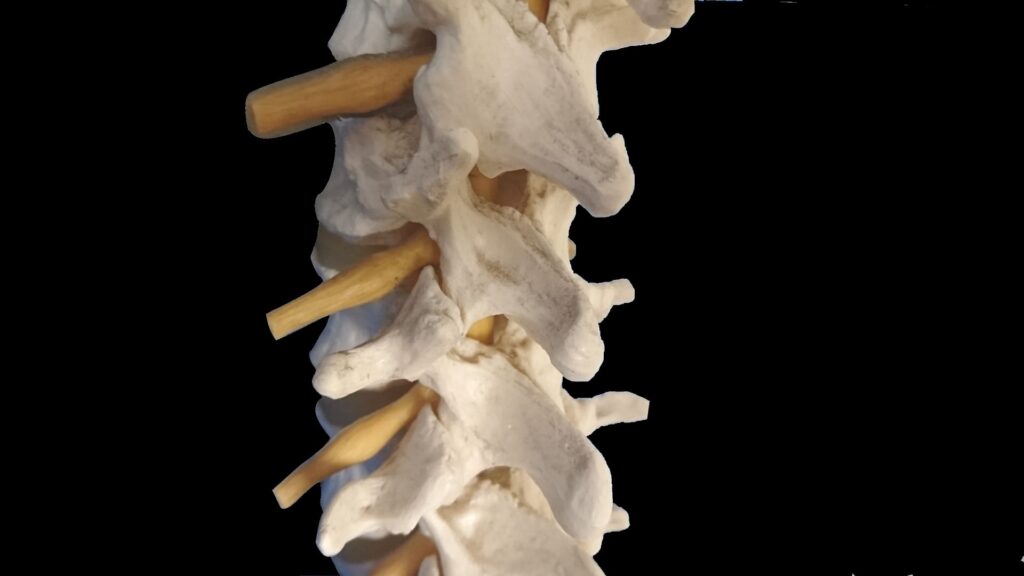

人体解剖学とは、解剖学のなかで組織学や細胞学を除いた、人体の器官や組織に関して研究する学問の事をいいます。

単に解剖学と呼ばれる事も多いですが、解剖学には動物解剖学と植物解剖学とがあり、このうち動物解剖学の一部としてあるのが人体解剖学になります。

骨格の構造や関節の可動域、筋肉の起始・停止を正確に理解していれば、個人の身体特性に合わせた無理のないトレーニングプログラムを組むことができます。代償動作(本来使われるべき筋肉とは別の筋肉が補って動いてしまうこと)を瞬時に見抜き、正しいフォームに導くことも可能になります。

具体的には、まず身体の土台である「骨格」から学び始めることをお勧めします。主要な骨の名前と位置、そして関節がどのように動くのか(屈曲、伸展、外転など)を最初に覚えます。骨格というフレームワークが頭に入ってから、次に個々の「筋肉」がどの骨からどの骨に付着しているのか(起始・停止)、そしてその筋肉が収縮するとどのような動き(作用)が起こるのかを学んでいきます。